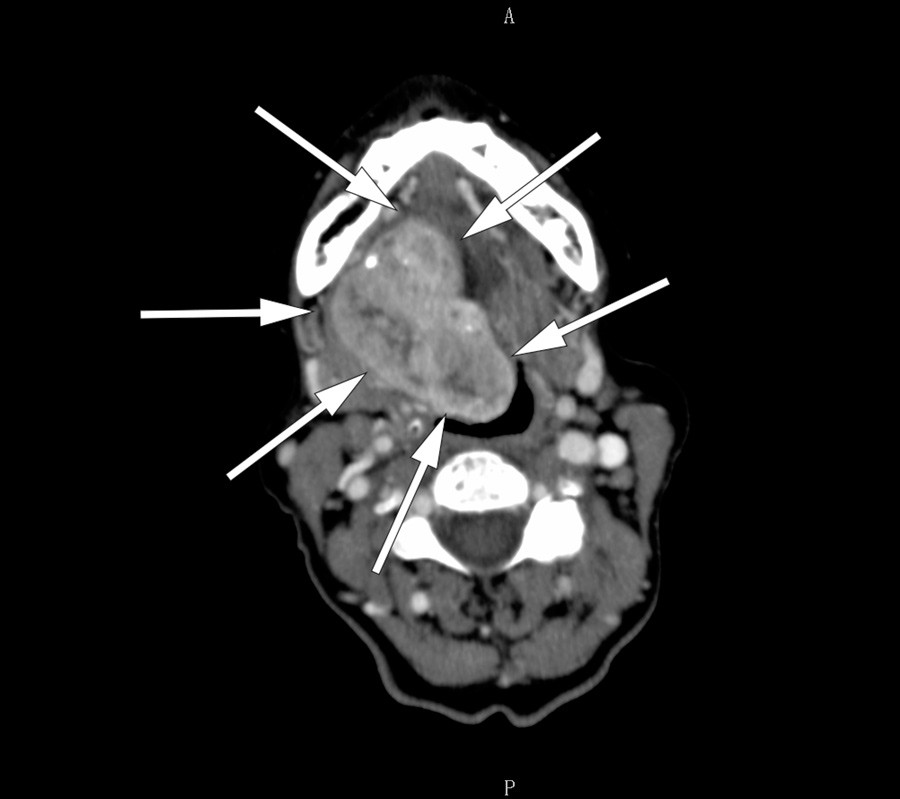

A CT neck scan using contrast medium (left) showed a large tumour in the floor of her mouth. An MRI neck scan with contrast (right) showed irregular contrast enhancement in the tumour. Fine-needle cytology revealed tissue most consistent with thyroid gland with no sign of malignancy. The findings indicated ectopic thyroid, and re-examination of the CT images showed an absence of thyroid tissue in the usual location. Blood tests showed that the patient was euthyreotic and negative for antithyroperoxidase and antithyroglobulin antibodies.